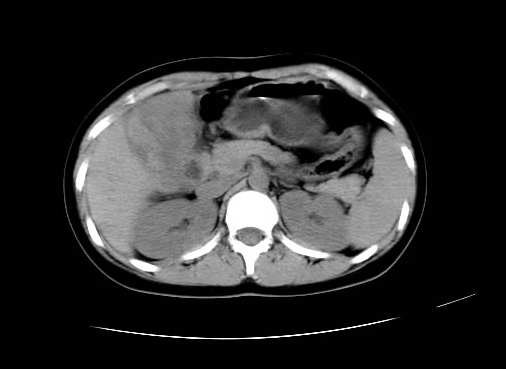

女 16岁  右上腹痛一天,无其他不适

肿块最大径位于十二指肠降段与水平段移行处,并且与肝脏压迹呈“0”形征,可以考虑位于肝外并与胃肠道关系紧密,考虑胃肠道间质瘤(gist)可能较大,须除外神经节起源肿瘤。

肿块与十二指肠关系密切,支持间质瘤诊断.肝脏与结肠均为受压改变.

右下腹巨大肿快,密度不均匀,内见坏死低密度区,边界清楚,与周边胀器明显有分界,未见强化,多考虑来源于间叶组织的良性肿物.

我坚决反对您的观点,该病例定位:横结肠肝曲与升结肠之间的肠系膜及部分肠壁。请看下图:

病灶巨大,少部分向肠腔内生长,大部分向长腔外生长。其密度不均匀,增强显示明显不均匀强化,并见有大片状始终不强化的不规则坏死液化区。虽然病灶中上部形态尚可,病人又如此年轻,但中下部形态、密度、强化特点强烈提示为恶性病灶。综上,我考虑本病例为:恶性胃肠道间质瘤。